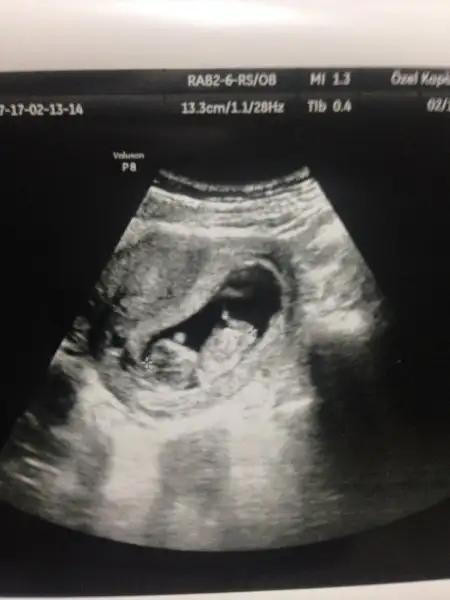

Eki Görüntüle 1953411 Kizlar bugun tekrar gittim doktora,8 haftalikken bebek kesenin sagindaydi.simdi 10 haftalik,cok kipirdak sanirim sola yaklasmis.bu kese ve cinsiyet konusu kac haftalikken dogru oluyor? Bidaha bakarmisniz bana

Cnm bu konu başkasınındı o zaman tek sağ sol olarak yorum yapılıyordu ama ben plasenta, kese ve bebek hangi yönde ağırlıktaysa ona göre yorum yapıyorum. Önemli olan ilk USG resmi olsun 6,7,8 haftalık